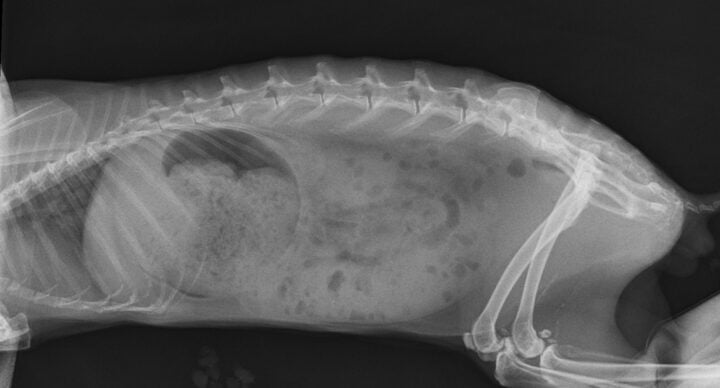

Radiography is an excellent tool to assess the presence of gastric dilation and intestinal obstruction. A retrospective study comparing radiographs of rabbits with gastrointestinal stasis and gastrointestinal obstruction identified several key features to differentiate between the two conditions (Debenham et al., 2019).

Cases of obstruction were more likely to have gastric distension where the sum of the height and length of the stomach was greater than or equal to the length from the first lumbar vertebra to the coxofemoral joint. Ninety-two percent of obstruction cases showed contact between the ventral aspect of the stomach and the ventral abdominal wall. In addition, most obstruction cases showed gastric contents consisting primarily of liquid with a “gas cap” (Figure 3A), whereas gastrointestinal stasis cases showed evidence of normal stomach ingesta (Figure 3B).

In cases of obstruction, gas in the small intestine but absent in the caecum is also a common finding (Huynh and Pignon, 2013).